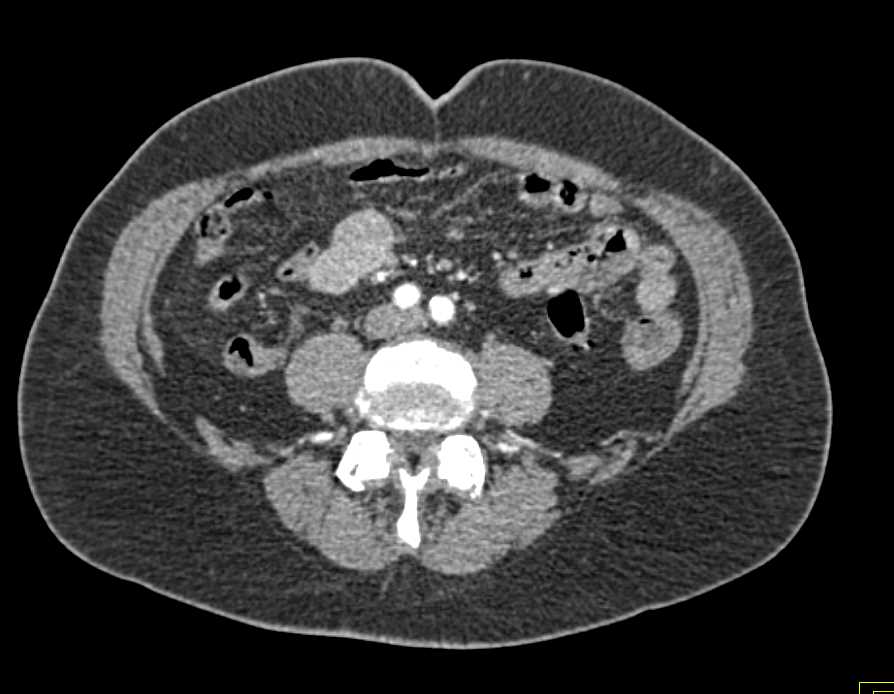

Carcinoid Tumor Root of Mesentery with Misty Mesentery and Vessel Encasement